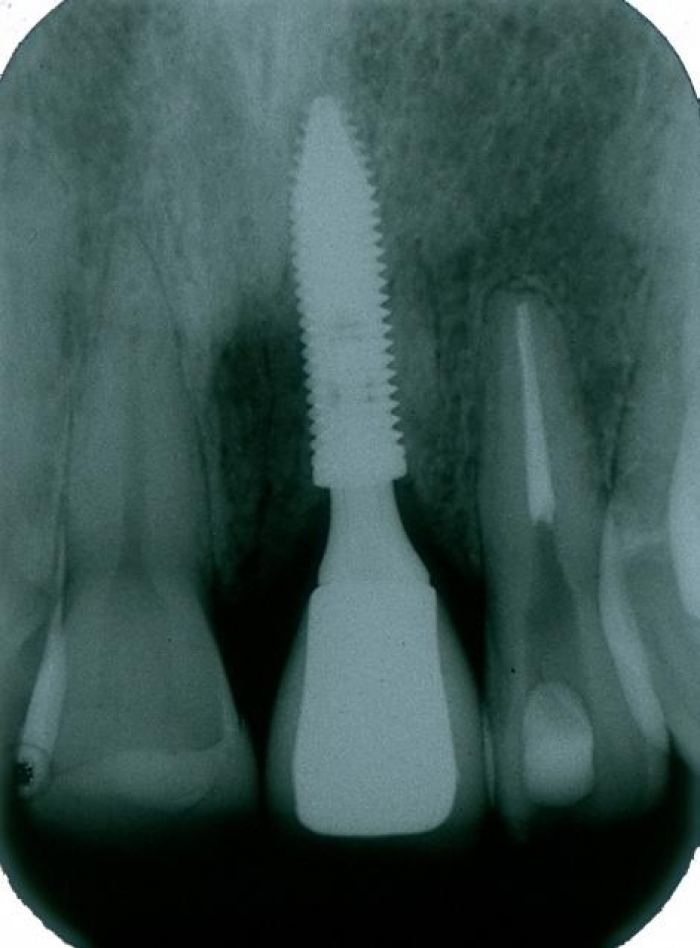

Raio X do implante instalado